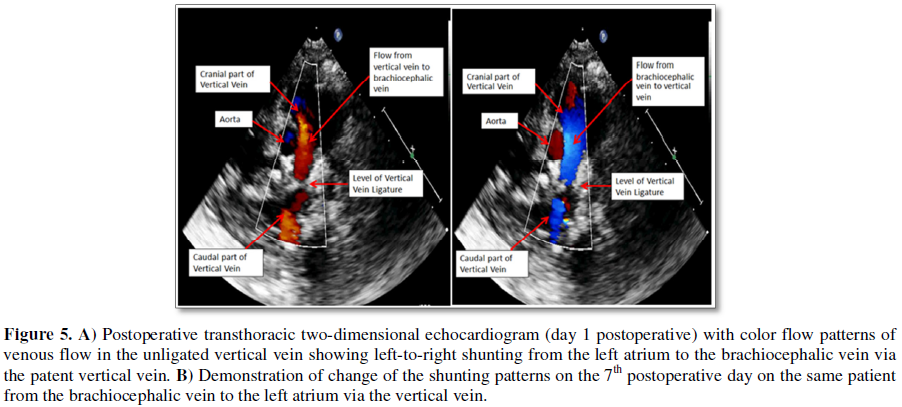

ligated category (p=0.03) [34,62]. All patients underwent serial

cross-sectional and Doppler echocardiographic evaluation in the postoperative

period and gradual process of vertical vein ligation at varying time intervals

between 5 and 25 days, as soon as right-to-left shunting through the vertical

vein disappeared (Figures 5A and 5B). None required anti-failure cardiac

medications [34,62].